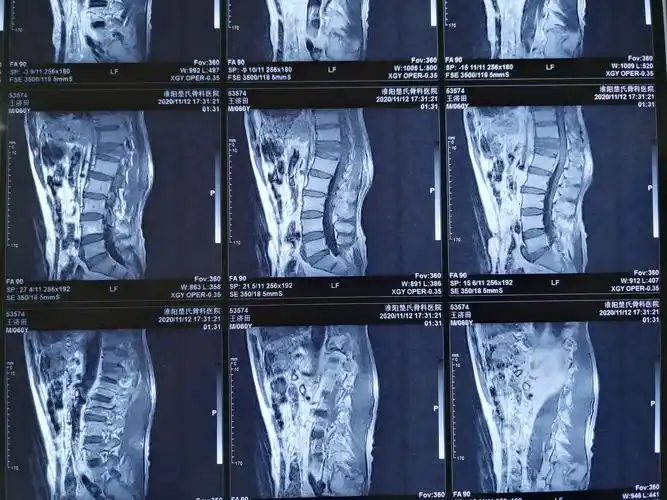

王济田胸12椎体chance骨折

外科成功为一名强直性脊柱炎胸椎chance骨折并截瘫患者完成高难度手术

chance骨折:为椎体 水平撕裂性损伤.也 属不稳定骨折,临床 较少见.